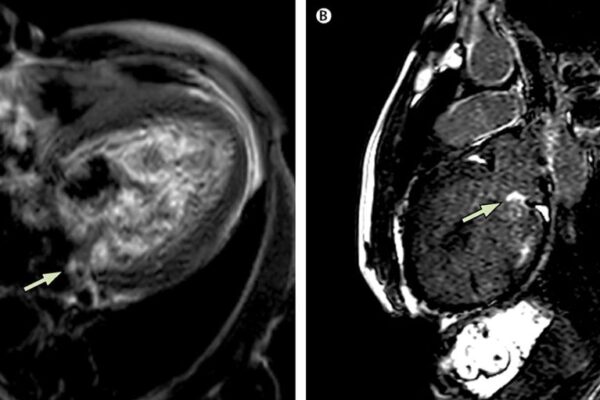

- Emar

- Kontrastlı Emar